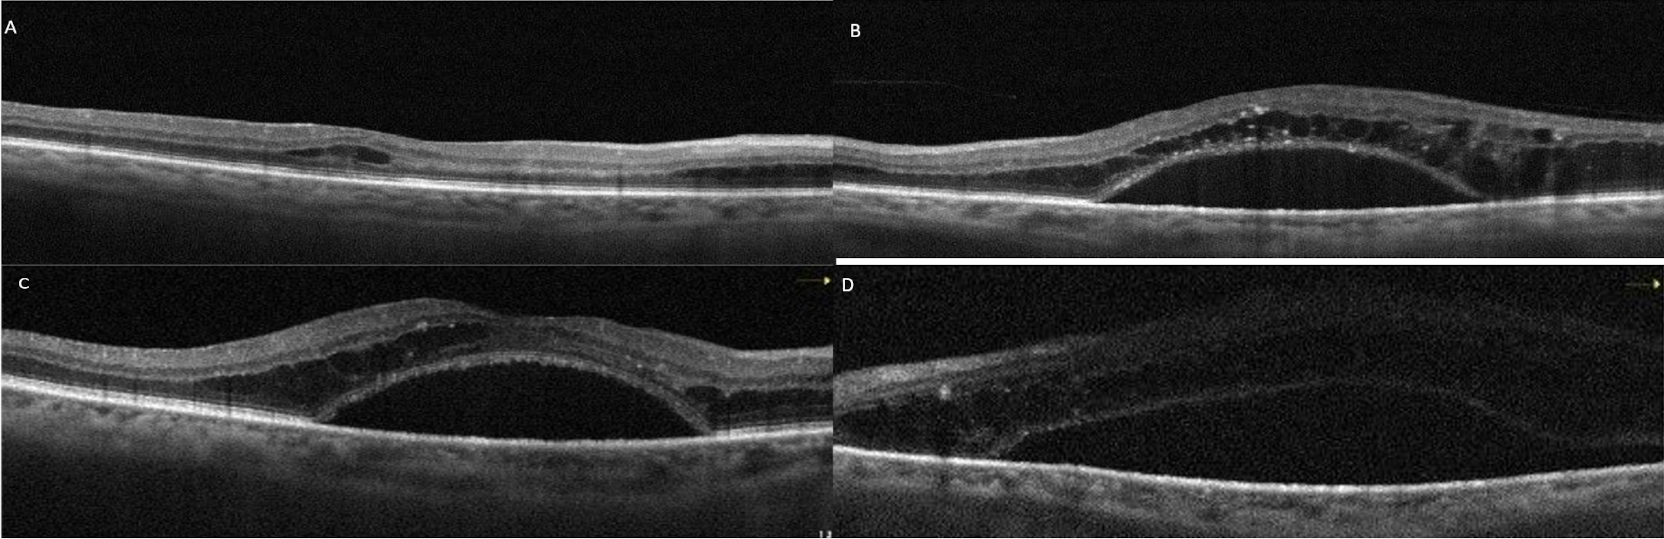

A 52-year-old male patient with a 12-year history of diabetes presented to our department reporting progressive visual impairment in both eyes. He had no other known systemic diseases. On ophthalmological examination, the best-corrected visual acuity (BCVA) was 20/50 in the right eye and 20/30 in the left eye with Snellen charts, bilateral biomicroscopic evaluations of anterior segments were normal, and intraocular pressure (IOP) measurements were within normal range for both eyes. Dilated fundus examination revealed widespread hemorrhages and microaneurysms in all quadrants of both retinas and laser spots, consistent with diabetic retinopathy (DR) (Figure 1A and B [Fig. 1]). Bilateral SRD and intraretinal fluid accumulation, which was more prominent in the left eye, were detected on OCT (Figure 1C and D [Fig. 1]). The patient was diagnosed with DR and DME; intravitreal bevacizumab injections were advised.

Figure 1: Case 1; color fundus and OCT images at initial presentation. Extensive retinal hemorrhages and microaneurysms with occasional laser spots are seen in right (A) and left (B) eyes. Significant subretinal fluid and intraretinal edema were also observed on simultaneous OCT images of the right (C) and the left (D) eyes.

Following three intravitreal bevacizumab injections administered to both eyes, the patient’s BCVA declined to 20/100 in the right eye and 20/60 in the left eye. OCT images showed a decrease in intraretinal fluid, but there was no regression in SRDs (Figure 2A and B [Fig. 2]). Continuing panretinal photocoagulation was scheduled due to retinal ischemia on fundus fluorescein angiography (FFA) (Figure 2C and D [Fig. 2]). However, since the persistence of the SRD, no apparent leakage at the macula on FFA (Figure 2C and D [Fig. 2]), photoreceptor shedding was initiated on OCT (Figure 2A and B [Fig. 2]), and the patient complained of increased weakness and fatigue, an internal medicine consultation was requested. Laboratory tests showed hemoglobulin 6.8 g/dl (normal range: 13.1–17.2 g/dl), albumin 23 g/l (normal range: 35–52 g/dl), erythrocyte sedimentation rate 140 mm/h (normal value: <15 mm/h), C-reactive protein 14.9 mg/l (normal value: <6 mg/l) and hemoglobin A1c 8.1% (normal range: 3.5–5.7%) in the blood sample, and there was +3 proteinuria in the urine. Lymphadenopathy was also detected in the left inguinal region. Abdominal computerized tomography revealed lytic bone lesions in the left iliac wing, right acetabulum and L3–L4 vertebral bodies. The patient was diagnosed with multiple myeloma (MM) based on protein electrophoresis and hematologic examination. He was subsequently started on systemic chemotherapy for MM and no additional injections were administered for macular edema. Following initiation of treatment, macular subretinal fluid gradually resolved bilaterally (Figure 3A–F [Fig. 3]). The final OCT examination, 1 year after the first presentation showed resolution of the serous macular detachment (Figure 3E and F [Fig. 3]). At that time BCVA was 20/80 in the right eye and 20/100 in the left eye.

Figure 2: Case 1; OCT and FFA images of the right (A, C) and left (B, D) eyes after the anti-VEGF upload therapy. Intraretinal edema has regressed, but subretinal fluid persists and photoreceptor shedding becomes more apparent. FFA shows bilateral large retinal ischemia.